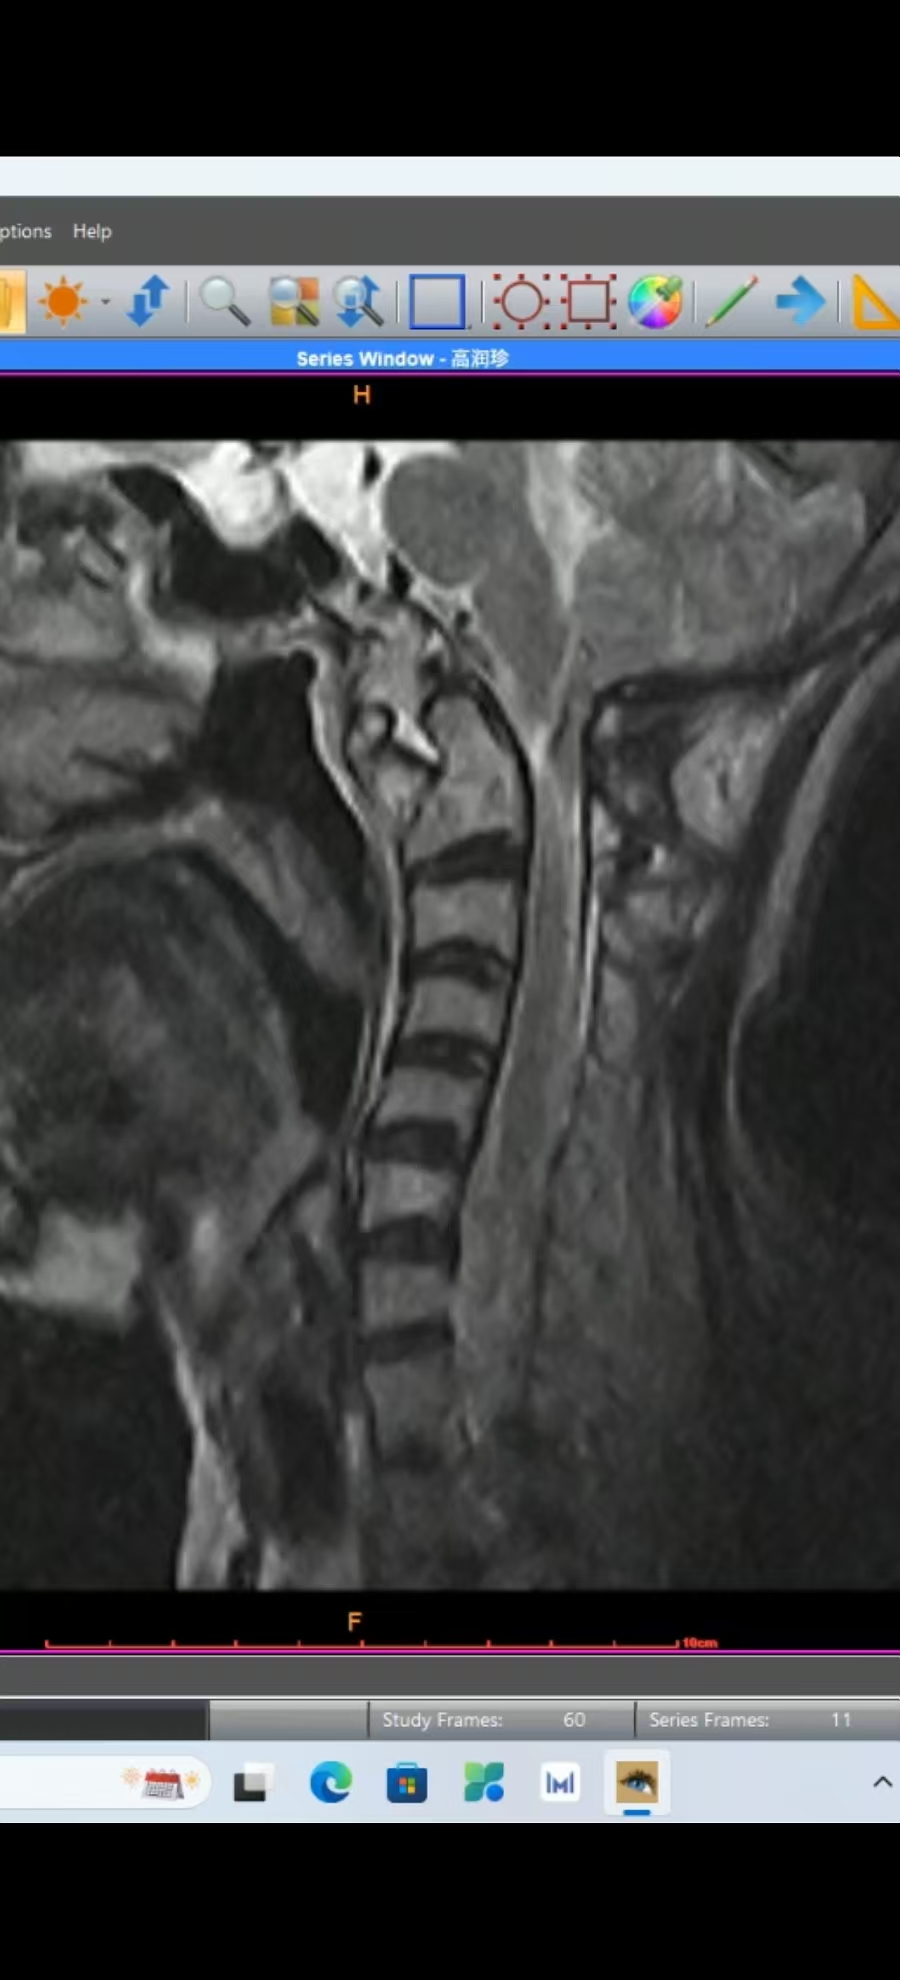

• 术后4个月,在天坛拍0.23低磁场核磁